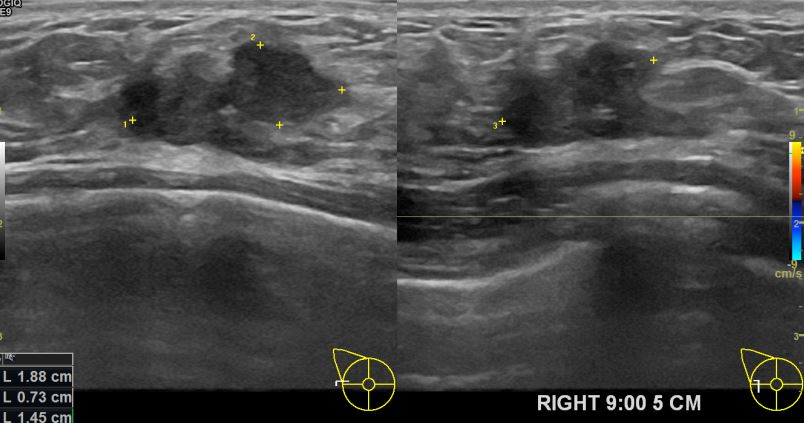

외부검사상 이상소견으로 내원하신 50대여성분으로 우측의 의심스러운혹 조직검사 시행후

유방암으로 진단되었읍니다.